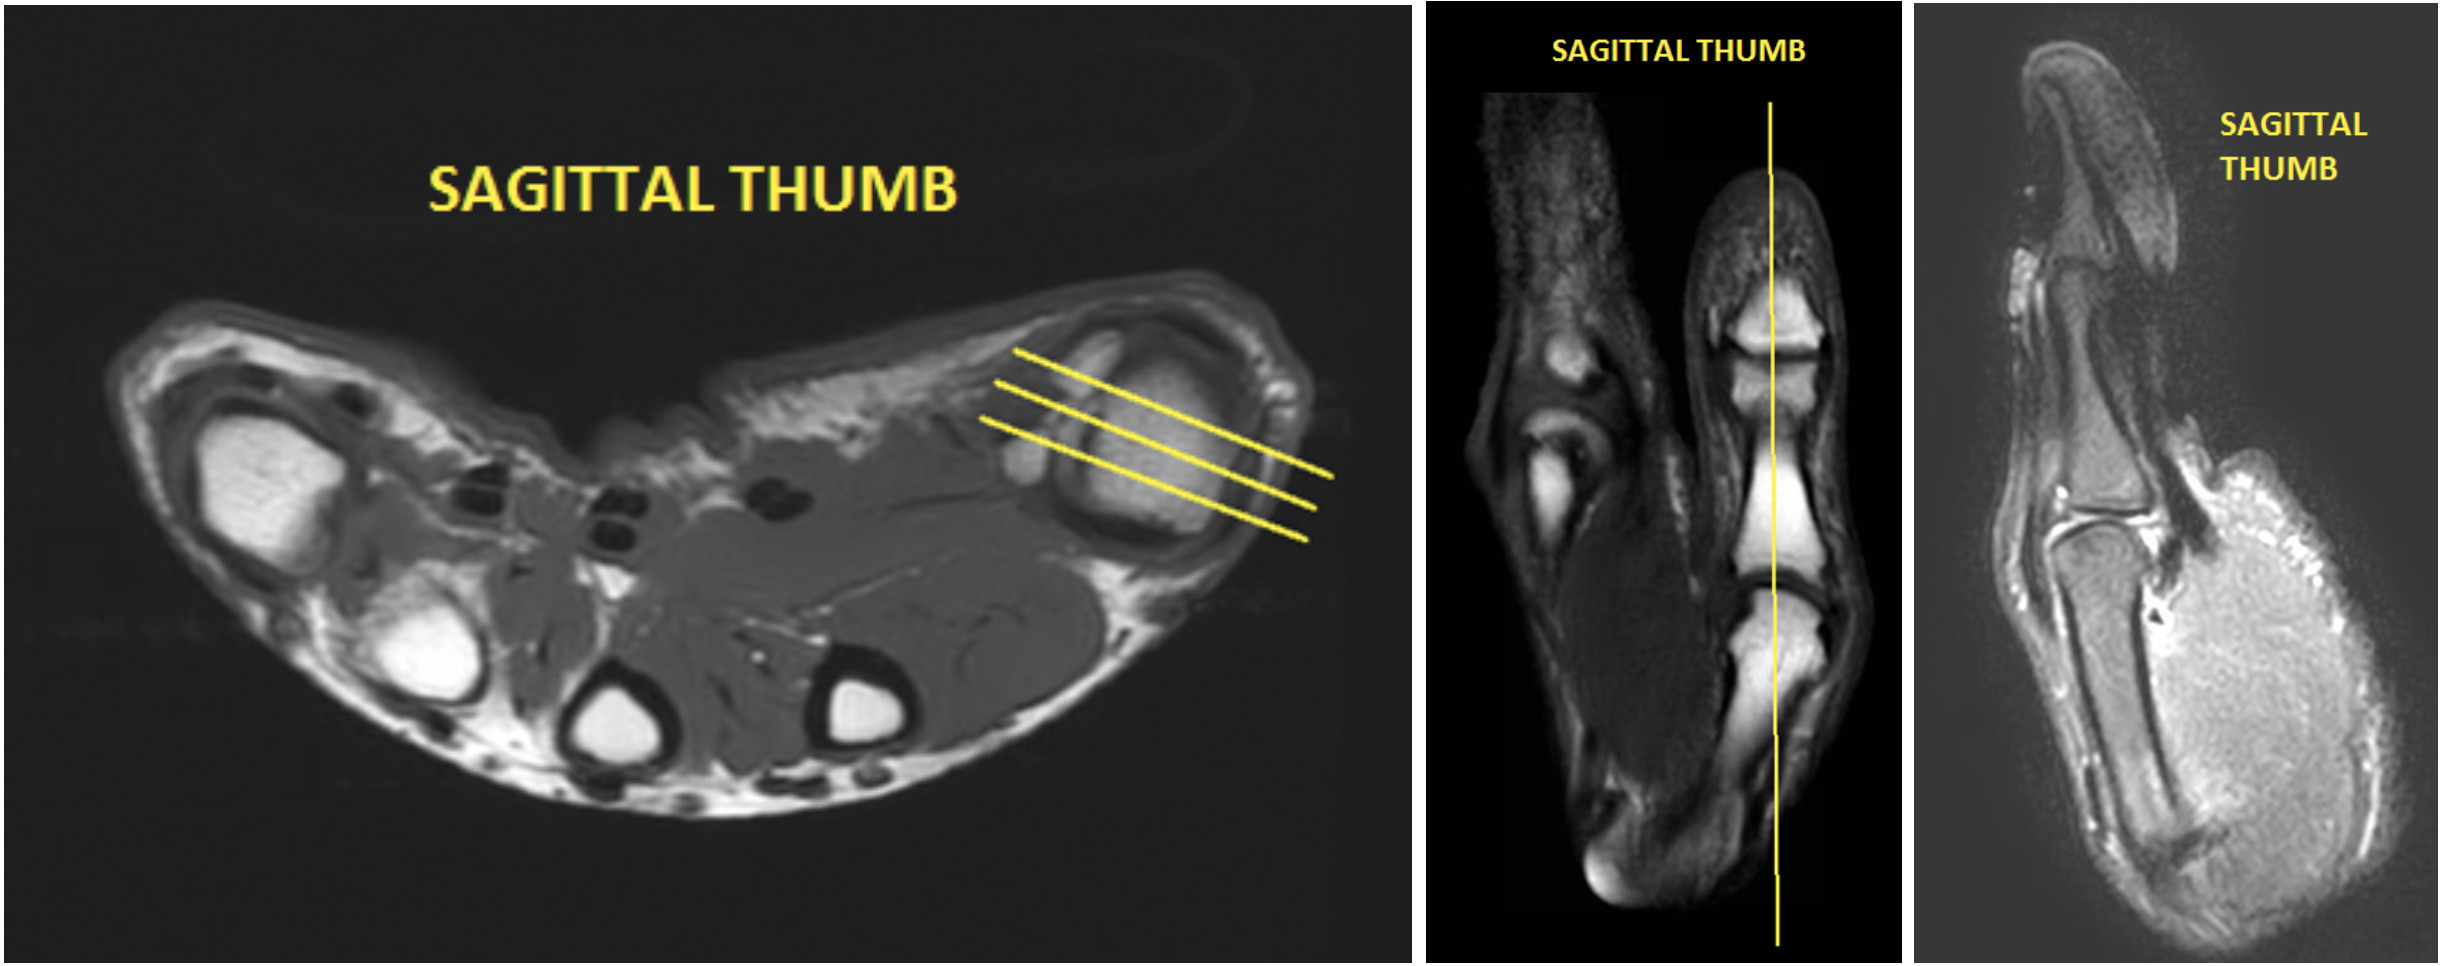

| SAG | Mid TE (40-50) T2 Fat sat | TSE | 3mm | 0.5mm | SPAIR | 12cm | Angle relative to Radio-Ulnar joint |

| SAG PRE(if giving gad for infection/osteo) | T1 | TSE | 3mm | 0.5mm | None | 12cm | Angle relative to Radio-Ulnar joint |